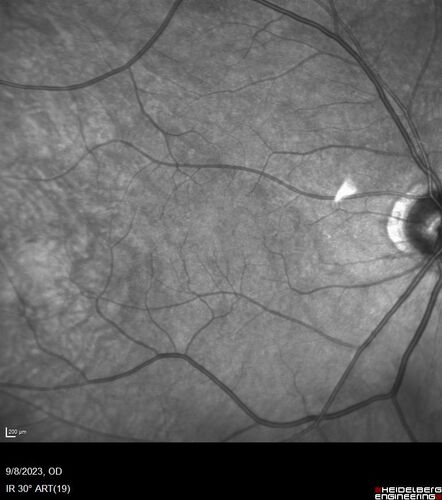

Paracentral acute middle maculopathy - isolated

83 year old man New spot in the vision yesterday left eye.

Medical Hx: Pure Hypercholesterolemia

Systemic Meds: Crestor.

VA OD: Dcc20/20

VA OS: Dcc20/20

IOP: TP: OD:19 OS:10